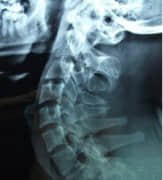

广东药学院附属第三医院骨科专家介绍,很多人对于股骨头坏死并不陌生,但是据调查显示,很多人对于股骨头坏死的病因并不是很了解,因此并没有做好相应的预防,延误了治疗的最佳时机,致残率非常高,给人们造成严重危害。因此我们先来了解一下导致股骨头坏死

治疗股骨头坏死需要做什么检查?广东药学院附属第三医院骨科专家指出,近几年里,有不少的人都饱受着股骨头坏死所带来的痛苦,尤其是年纪大的老年人,这种病对老年人来说对他们的健康是非常不利的,所以发现疾病要及时的去治疗。那么,治疗股骨头坏死需要做